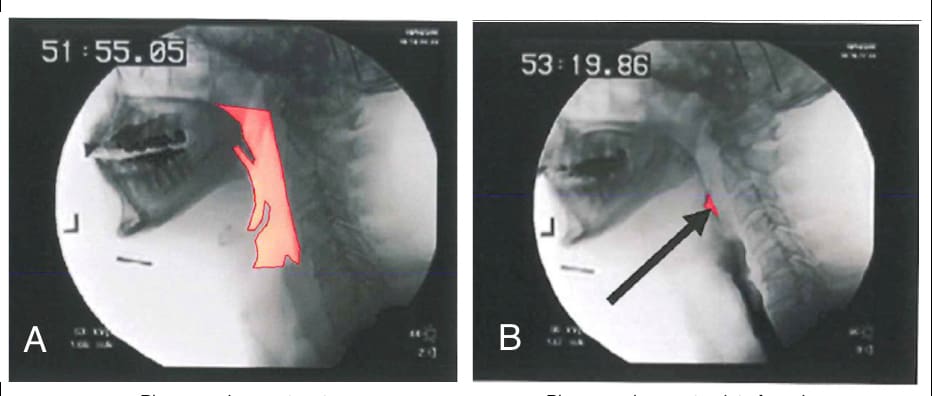

figure-2-pharyngeal-squeeze